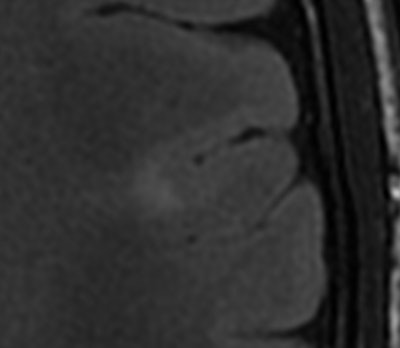

Cortex-isointense signal abnormalities in the subcortical white matter on T2-weighted axial sequence corresponding to heterotopia.Four basic sequences will answer most of the questions aimed at ruling out common malformations in children with developmental delay, Ertl-Wagner told delegates. These are T2-weighted axial sequence, T2-weighted sagittal sequence, FLAIR sequences, and T1-weighted inversion-recovery sequences. Motion correction sequences can be especially helpful when imaging children. In addition, 3D sequences can aid in detecting small abnormalities, in patients with epilepsy, for example.